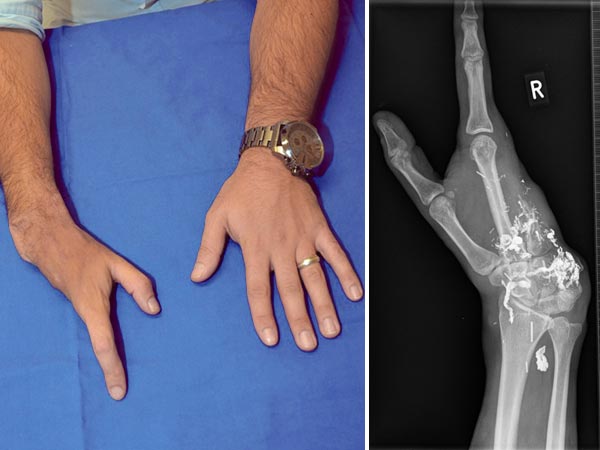

Bereits bei der Geburt fand sich eine Veränderung am Ringfinger. Es wurde eine „Angiodysplasie mit ausgedehnten Shunts“ diagnostiziert und im Alter von 3 Jahren wegen rezidivierender Blutungen aus einem Ulkus der Fingerkuppe der Ringfinger auswärts amputiert. Diese Fotos wurden im 12. Lebensjahr aufgenommen. Damals zeitweise Schmerzen in der Hohlhand. Rötliche, überwärmte Raumforderung in der Hohlhand mit Venenektasien an der Hand, tastbarer arterieller Puls und Schwirren, weiche elastische Schwellung in der palmaren Mittelhand und Hypothenar.

Danach Stabilisierung mit deutlicher Besserung der Lebensqualität, keine Schmerzen. Dieses Foto entstand im Alter von 25 Jahren. Anfängliche Phantomschmerzen verminderten sich spontan von einmal wöchentlich auf einmal alle 2 Monate. Der Patient ist wieder sportlich aktiv mit Kickboxen und Schwimmen. Ausbildung zum Maschinenbauingeneur abgeschlossen. Er trägt jetzt permanent einen Kompressionshandschuh. Im Röntgenbild rechts noch Teile des alten Embolisats sichtbar, die die AVM-Reste verschlossen haben.

Im 25. Lebensjahr schreibt der Patient unverändert mit der rechten Hand. Eher kraftarmer Spitzgriff zwischen Daumen und Zeigefinger von 1 kg gegenüber links 7 kg.

Es findet sich jedoch eine freie Beweglichkeit der verbliebenen Finger bis auf eine geringe Einschränkung der Zeigefingerstreckung durch Beugesehnenverkürzung. Normale Sensibilität. Kein Anhalt auf Rezidiv zu diesem Zeitpunkt.